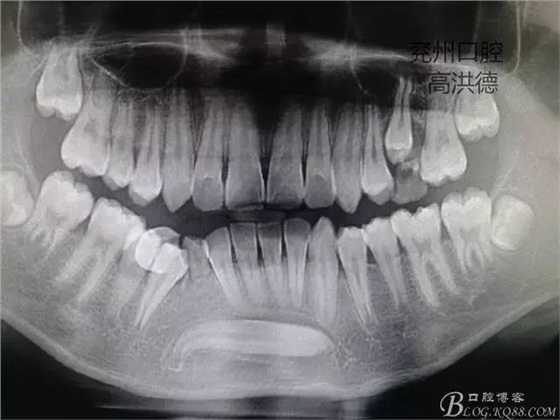

曲面斷層片顯示